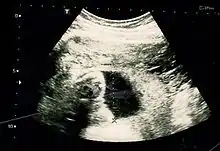

Obstetric ultrasonography is routinely used for dating the gestational age of a pregnancy from the size of the fetus, determine the number of fetuses and placentae, evaluate for an ectopic pregnancy and first trimester bleeding, the most accurate dating being in first trimester before the growth of the foetus has been significantly influenced by other factors. Ultrasound is also used for detecting congenital anomalies (or other foetal anomalies) and determining the biophysical profiles (BPP), which are generally easier to detect in the second trimester when the foetal structures are larger and more developed. Specialised ultrasound equipment can also evaluate the blood flow velocity in the umbilical cord, looking to detect a decrease/absence/reversal or diastolic blood flow in the umbilical artery.

X-rays and computerized tomography (CT) are not used, especially in the first trimester, due to the ionizing radiation, which has teratogenic effects on the foetus. No effects of magnetic resonance imaging (MRI) on the foetus have been demonstrated,[4] but this technique is too expensive for routine observation. Instead, obstetric ultrasonography is the imaging method of choice in the first trimester and throughout the pregnancy, because it emits no radiation, is portable, and allows for realtime imaging.

The safety of frequent ultrasound scanning has not been confirmed. Despite this, increasing numbers of women are choosing to have additional scans for no medical purpose, such as gender scans, 3D and 4D scans. A normal gestation would reveal a gestational sac, yolk sac, and fetal pole. The gestational age can be assessed by evaluating the mean gestational sac diameter (MGD) before week 6, and the crown-rump length after week 6. Multiple gestation is evaluated by the number of placentae and amniotic sacs present.